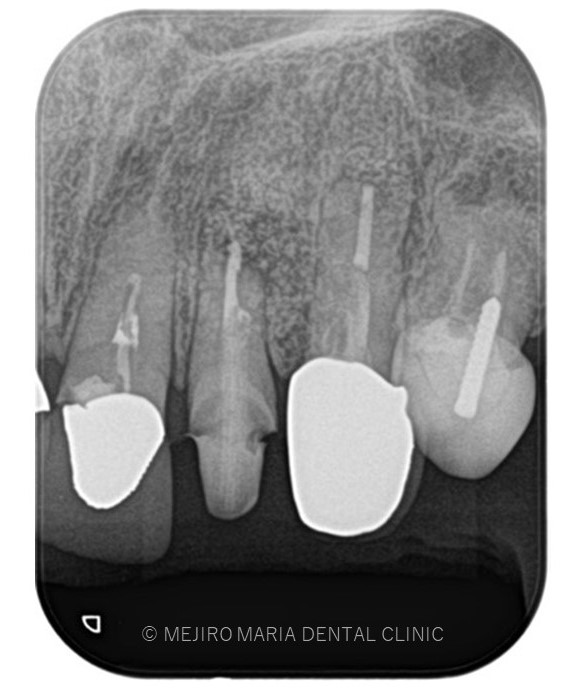

でのリカバリー_歯根端切除術直後のレントゲン画像.jpg)

でのリカバリー_術後3ヶ月後のレントゲン画像.jpg)

レントゲン写真より根尖部の骨は3ヶ月で順調に再生していると考えられます。

また、術前に訴えておられた違和感や腫脹、瘻孔は消失しており、現時点で経過は良好であると判断しています。

引き続き経過観察を継続していきます。